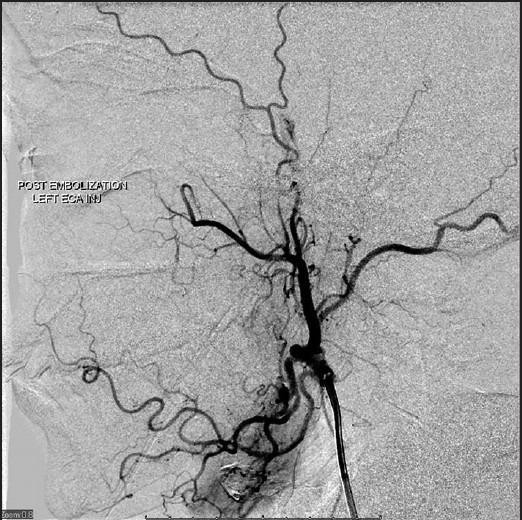

Diabetes plus third nerve palsy not always diabetic third nerve palsy.